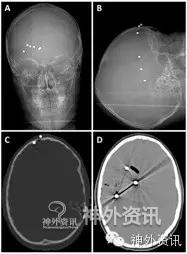

图1. 病例2患儿在取出BB弹之前的影像学检查图像。A. X线正位片和 B. X线侧位片:4枚BB弹丸进入颅内,2枚留在皮下;C. CT骨窗轴位片:额部颅骨骨折,BB弹丸由此进入颅内; D. CT轴位片:颅内3枚BB弹丸以及颅内积气。